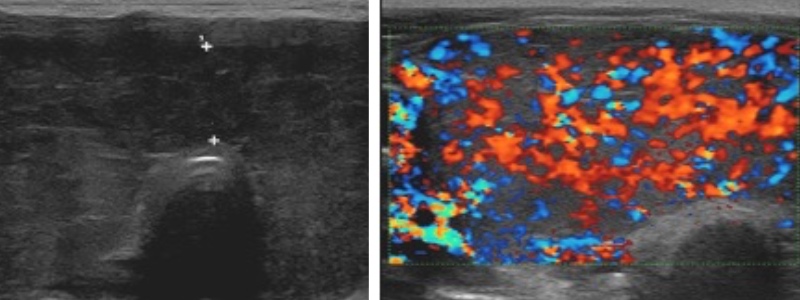

- goitre hypoéchogène homogène, Ac anti-récepteur de la TSH (TRAK)

- hypervascularisation intense > 1 m/s ("thyroid inferno" > 50% parenchyme)

- récidive : plus hétérogène et moins vascularisé